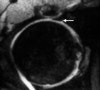

- Axial section

Axial oblique T2 gradient echo MR arthrogram demonstrating anterior and posterior portions of acetabular labrum.

Note that there is some heterogeneous signal within the intact labrum which may represent myxoid degeneration.